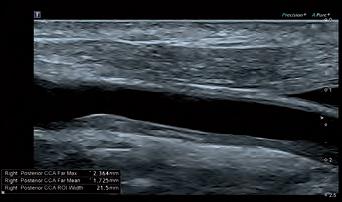

Ultrasound

To unlock sleek, crystal-clear imagery and outstanding clinical precision, Canon Medical UK are also supplying three Aplio i800 Prism Edition Ultrasound Systems to the Games. The Ultrasound scanners’ revolutionary iBeam architecture with unparalleled processing power provides exceptional imaging clarity and definition while significantly enhancing penetration. The increased power and sensitivity of our scanners will facilitate the evaluation of the athletes’ musculoskeletal structures, including early detection of potential injuries to subcutaneous tissue, muscle, tendons, ligaments and nerves.

Fig 2: Canon Medical Vantage Galan 3T MRI acquired Axial PD Fat Supressed image of the right ankle demonstrating a grade 1/2 tear of the anterior talofibular ligament (ATFL).